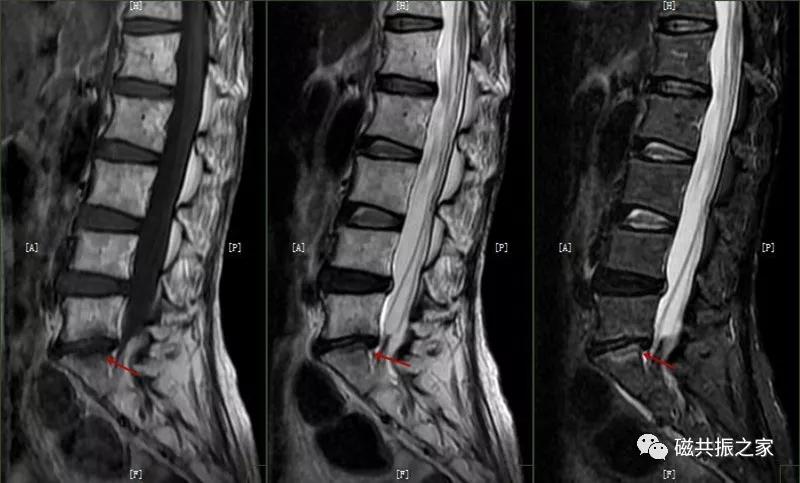

12.休门病/许莫尔结节/椎体边缘骨

休门病(Scheuermann,sdisease),主要由椎板骨软骨炎引起骨生长障碍,常见于青少年胸腰椎脊柱病变。

主要表现:椎体发育异常,椎体楔形改变,高度变低,前后径正常,常形成脊柱后凸畸形。

在矢状面上T1WI和T2WI显示各椎体楔形变,椎体高度减小,椎间隙变窄。椎体后1/3区呈多发性小骨质凹陷的Schmorl结节改变,髓核组织突入其中,边缘清楚,常呈上下对称分布,青少年病变周围可见长T1长T2信号,提示骨小梁水肿。

许莫尔结节(Schmorl,snodes),是休门病的一个病例征象。1930年Schmorl对照检查8000例尸检和X线发现椎体生长板发育不完善,或后天外伤致椎间盘突入椎体骨松质内,形成椎体压迹,是休门病的主要征象之一。除休门病外,其他的原因引起的生长板破坏,也可能产生Schmorl结节样改变。

矢状面显示椎体上或下椎间盘面异常信号,常呈长T,长T2信号,见髓核信号突入椎体内,常伴椎间隙变窄,常见于L3~S1椎体。

椎体边缘骨,类似于Schmorl改变,一类是椎体生长板和椎体二次骨化中心软骨发育异常,致其不能完全愈合,造成的椎间盘疝入其间,形成边缘体的椎体边缘骨。

另一类是椎体后缘骨内软骨结节,椎间盘疝入骨内,形成椎体后缘的Schmorl结节样改变,椎体终板及髓核等突入其中,椎体骨质增生,常见于L4、L5椎体下缘。